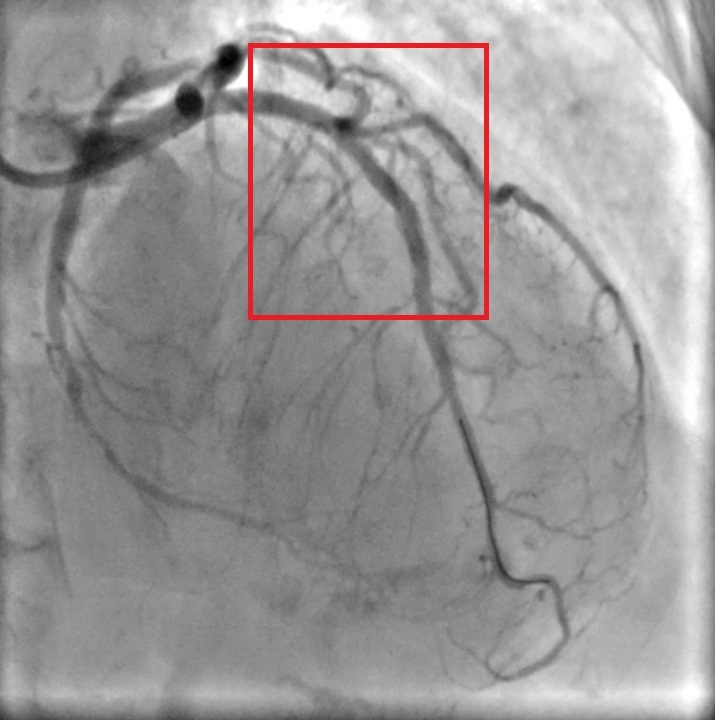

Hình ảnh của bệnh nhân được chụp lại sau khi các y, bác sỹ Bệnh viện đa khoa thành phố Vinh can thiệp y khoa cứu sống người bệnh

Theo các bác sĩ tim mạch, nguyên nhân phổ biến nhất của tình trạng tắc nghẽn là xơ vữa động mạch. Quá trình này diễn ra âm thầm từ sau tuổi 30 khi cholesterol, canxi và các mảnh vỡ tế bào tích tụ trong thành mạch, làm hẹp lòng mạch và dễ vỡ, dẫn đến tắc mạch cấp. Ngay khi ổn định tình trạng ban đầu, người bệnh được chuyển sang phòng can thiệp tim mạch để chụp mạch vành bằng DSA. Kết quả cho thấy: Hẹp 90% động mạch liên thất trước (LAD) đoạn I–II do xơ vữa vôi hóa nặng, Hẹp 50% nhánh mũ (LCx) đoạn xa.

Xác định đây là tổn thương nặng, nguy cơ tử vong cao nếu không tái thông kịp thời, ekip can thiệp tim mạch đã nhanh chóng tiến hành nong và đặt stent phủ thuốc LAD I–II. Thủ thuật được thực hiện thành công, dòng máu nuôi tim được khôi phục, huyết động người bệnh ổn định ngay sau can thiệp.